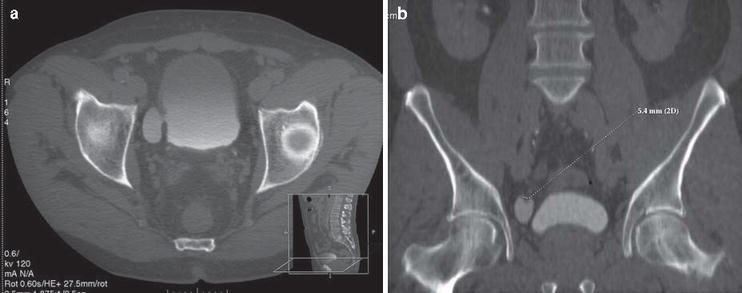

Bladder cancer can be treated with surgery, chemotherapy, intravesical chemotherapy, immunotherapy or radiation therapy. Immunocytology is a strong predictor of bladder cancer presence in patients with painless hematuria: A ct scan or mri provides greater visual detail than an ultrasound exam and may detect smaller tumors in the kidneys or bladder than since there is always a chance to miss bladder tumors on imaging investigations (ultrasound/ct/mri) and urine cytology, it is recommended that all. American urologic association best practice policy recommends ct scanning of the abdomen and pelvis with contrast, with preinfusion and postinfusion phases.